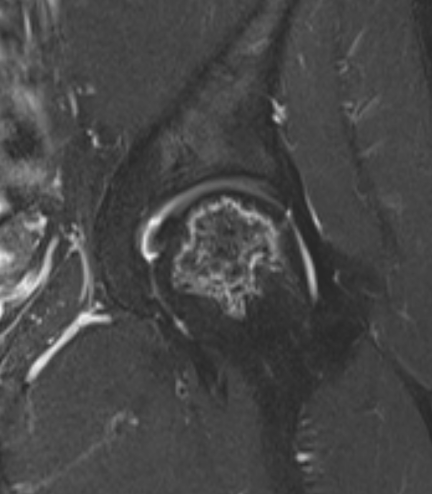

Osteotomy

Theory

Move the avascular segment away from weight-bearing area

- must have sufficient intact femoral head to bear weight upon

Indications

Young patient

Stage III / no osteoarthritis

Small lesion: CNA <200°

Not on steroids

Technique

CT / MRI decide osteotomy direction

- typically anterolateral AVN

- undergoes a varus flexion intertrochanteric osteotomy

Results

- 113 hips undergoing transtrochanteric rotational osteotomy

- 63% survival at 110 months

- age > 40, stage III, CNA > 2000 and BMI > 24 poor prognostic factors